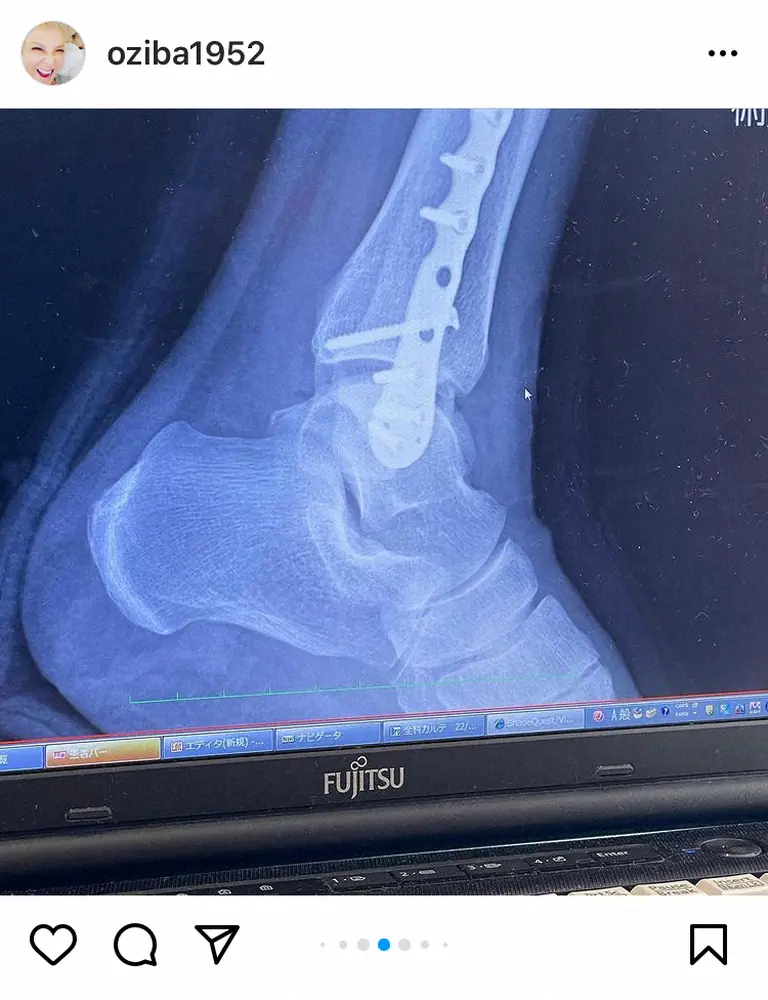

【画像・写真】池畑慎之介 22日に退院へ「チタンプレート入れて、ビス8本 震えます…」 ゴルフで転倒し左足首骨折

池畑慎之介インスタグラム(@oziba1952)から